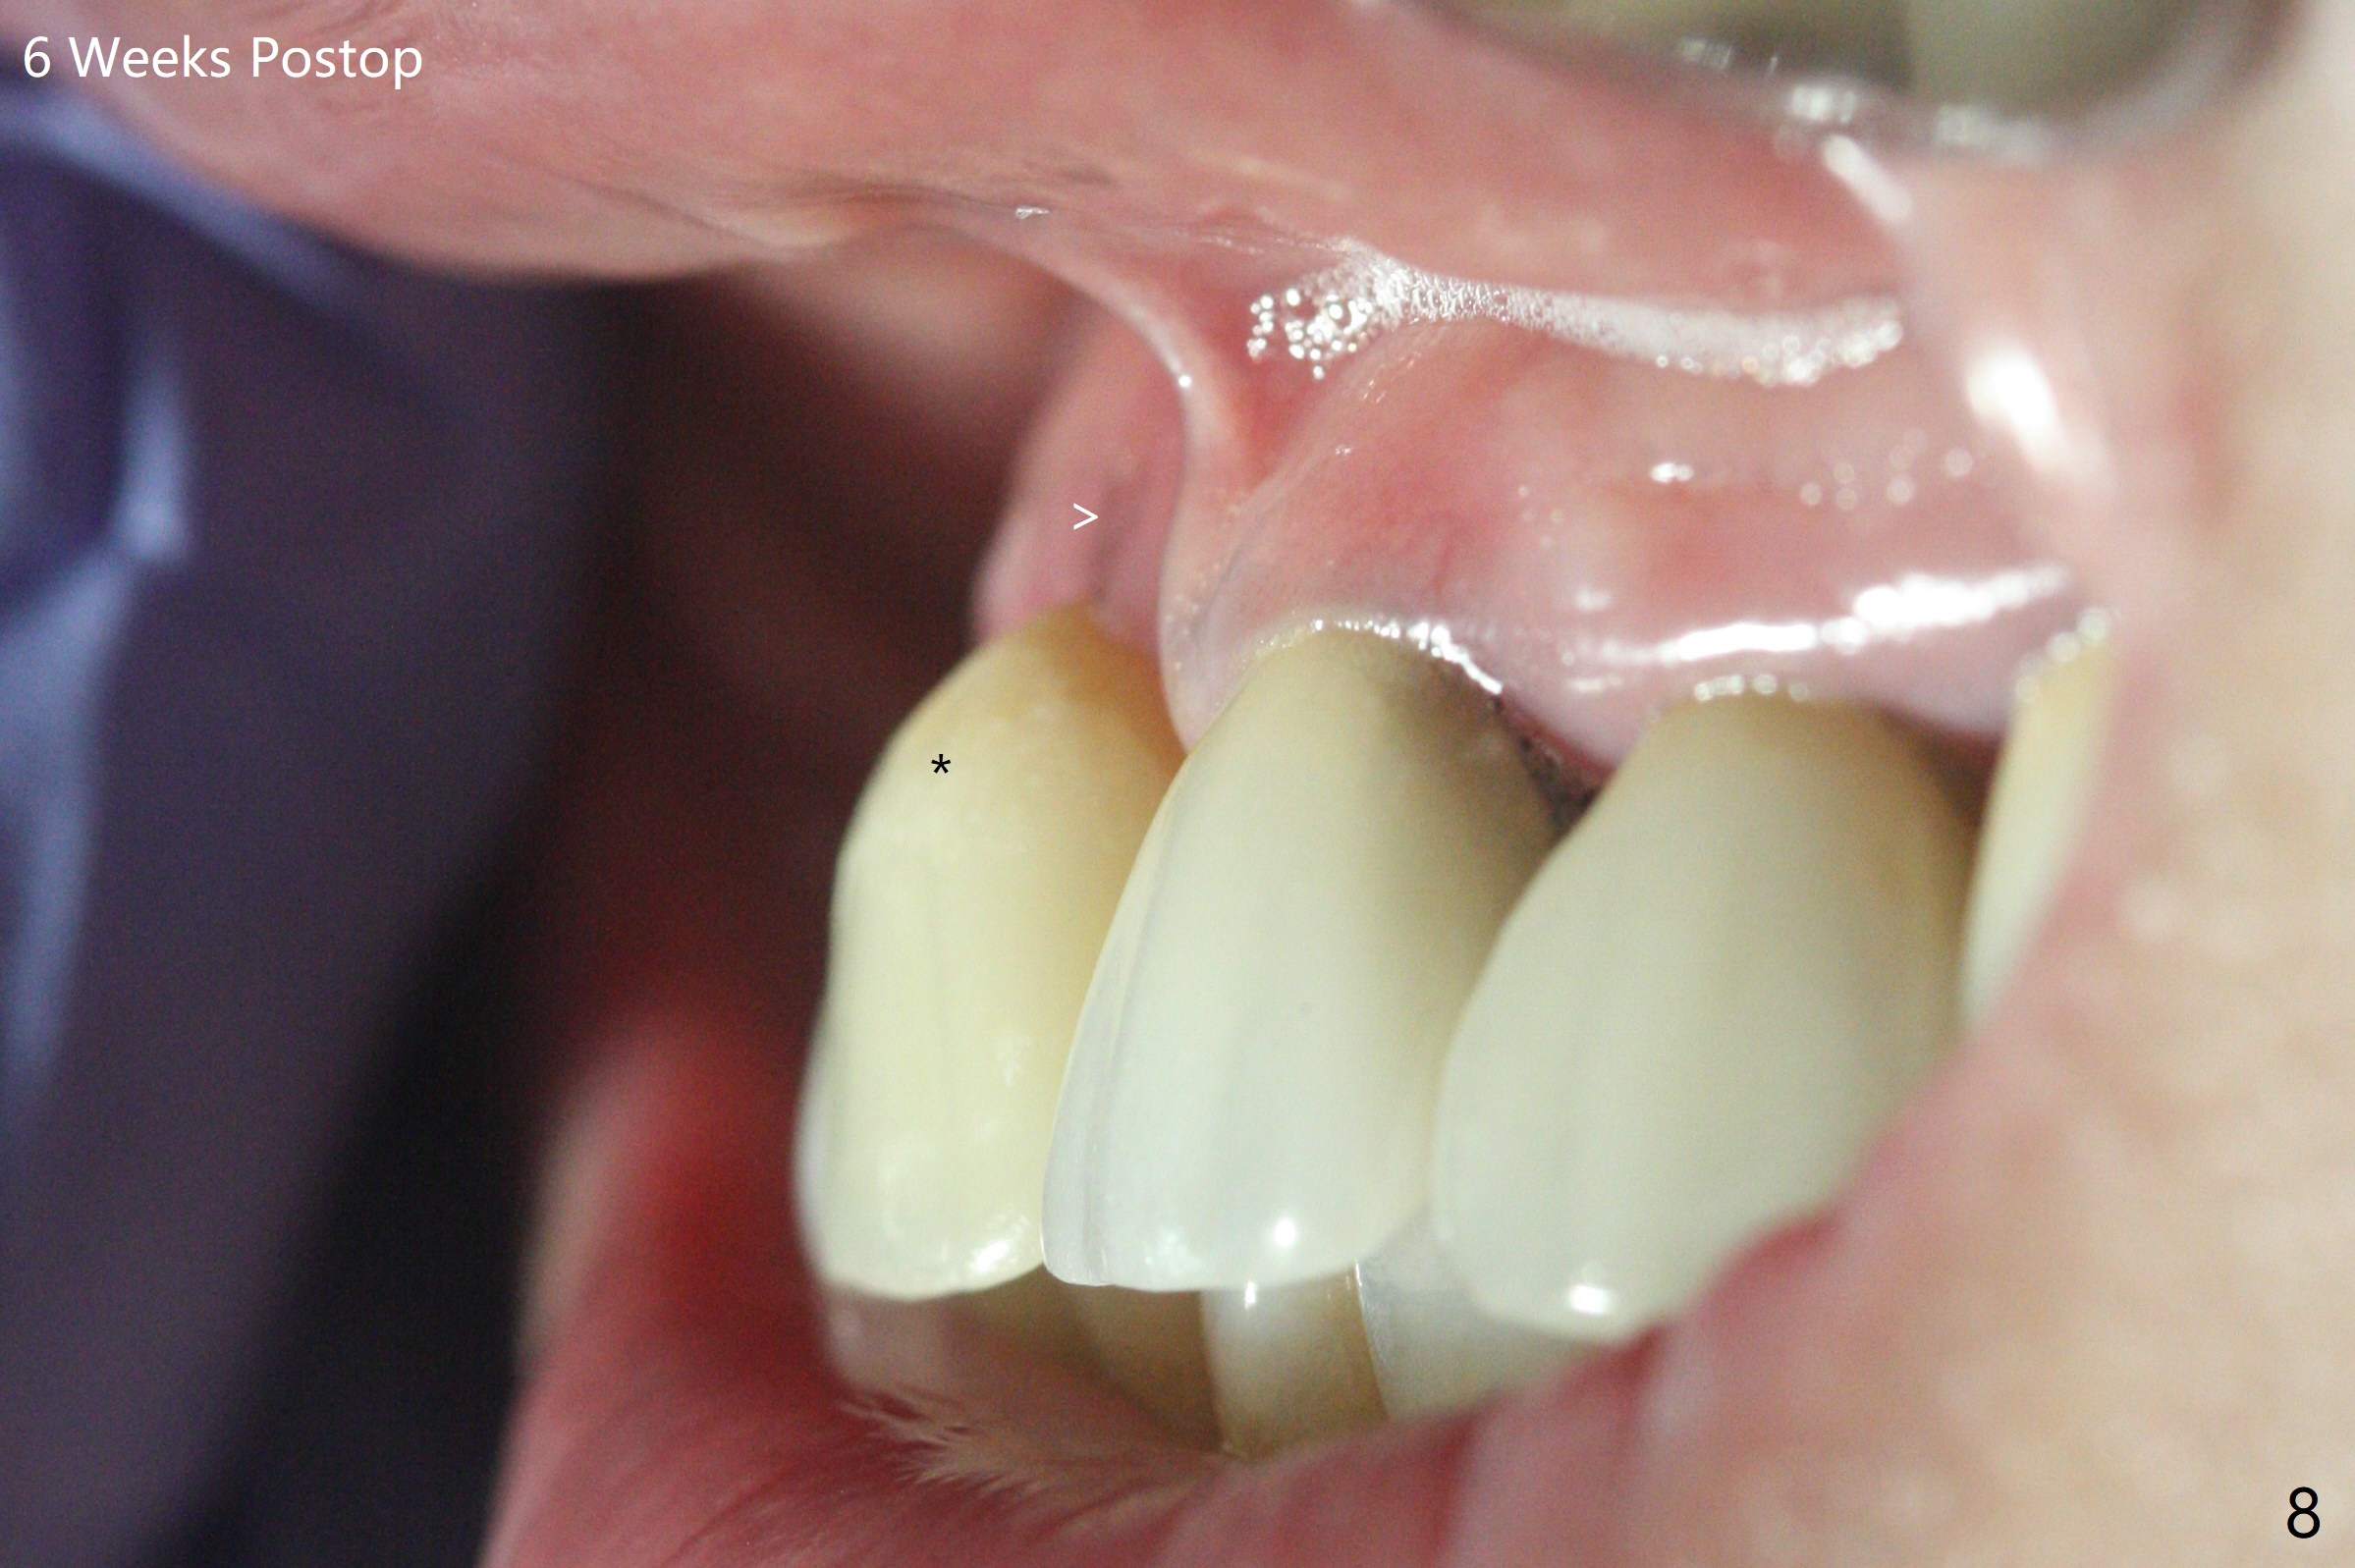

徒手初步钻洞显示方位不对(图一),重新钻洞方位尚可,好像接近鼻底(图二:红线);植入3x11.5毫米一段式植体(图三),3-5个螺纹暴露,植体似乎接近鼻底;旋转植体三趟,植体仿佛卡人鼻底,扭力大约35Ncm,植入粘性骨粉(图四,五:*)前,塞入PRF膜,紧贴颊侧粘膜,促进瘘道愈合。骨粉不仅围绕植体,而且紧贴邻牙牙根(图六(第二轮植骨:overgrafting):<)。病人术后第二周开始使用水牙线,术后三周牙龈健康多了,瘘道消失(图七)。术后六周颊侧骨壁开始塌陷(图八:>),临时牙冠颊侧颈部显得隆起(*)。调整后,牙冠外形改善(图十一至十三),取模前颊侧牙龈缘有可能下降,两个中切牙龈缘可能一致。术后3.5个月骨粉形态(图十四)与术后即刻(图六)有所不同。颊侧牙龈仍红肿轻度触痛(图十五),可能因为临时牙冠不利于局部卫生,所以决定取模制作永久性牙冠。粘固时使用临时胶水,并且涂抗菌素。另外一个可能因素是颊侧骨板薄(图十六:*),细菌感染植体螺纹,永久性牙冠粘固前,拍摄CT(放置cotton roll),必要时,植骨。永久性牙冠远中有缝隙,为了预防病人后悔,使用临时性粘固剂固定(图十七)。Return to No Caries DIO 下一个病例 一段式植体边缘制备 导板与内提升 Xin Wei, DDS, PhD, MS 1st edition 12/22/2020, last revision 06/15/2021